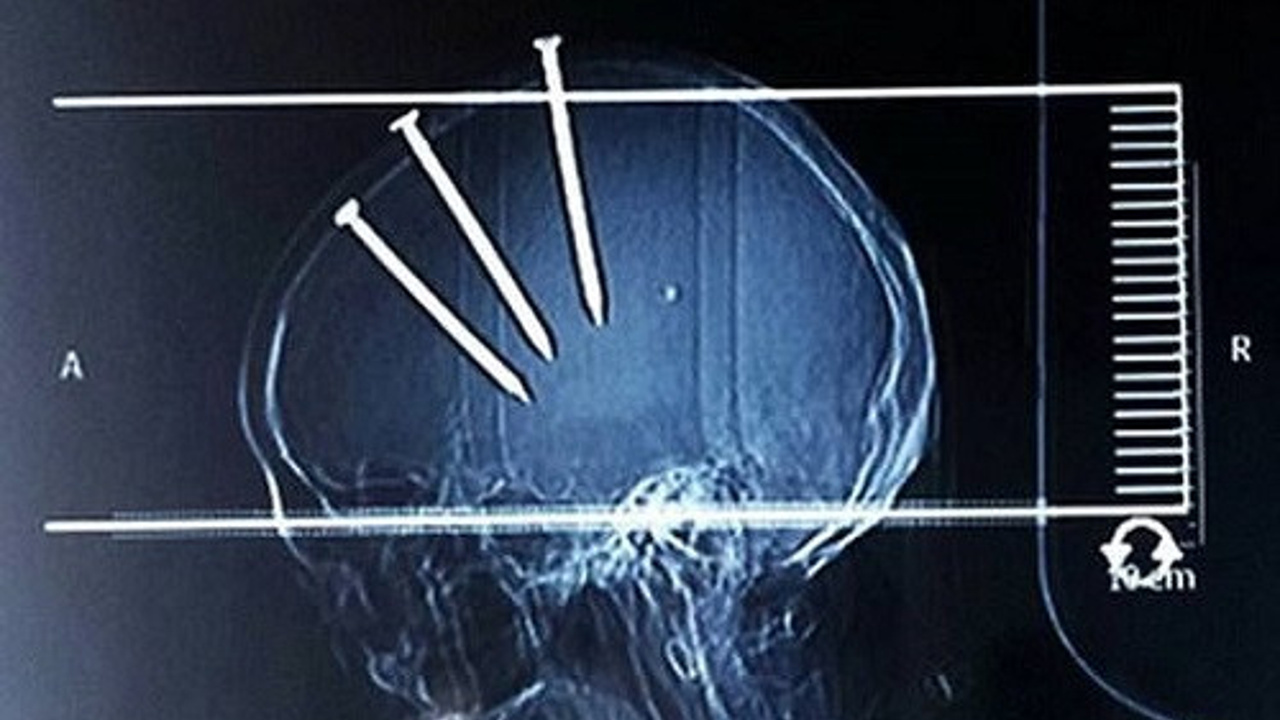

Hemen ameliyata alınan adamın başındaki çiviler teker teker çıkarıldı.... Yaşamaları mucize olan insanlar!

Hemen ameliyata alınan adamın başındaki çiviler teker teker çıkarıldı...

Çinli bir adam hastaneye getirildiğinde bu görüntüsü ile herkesi şaşırttı..

Çivilerin başları açıkça dışarıdan bile görünürken doktorlar Çinli adamın röntgenini çekti ve 3 koca çivi ile karşılaştı...